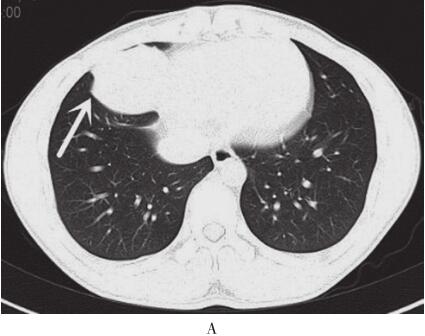

图2 2012年11月15日胸部CT平扫+强化

A.右肺中叶内侧段可见大小约5.7cm×5.0cm软组织肿块,有浅分叶,边缘清晰;B、C.双肺可见多发大小不等结节灶;D.肿块增强扫描呈中度强化